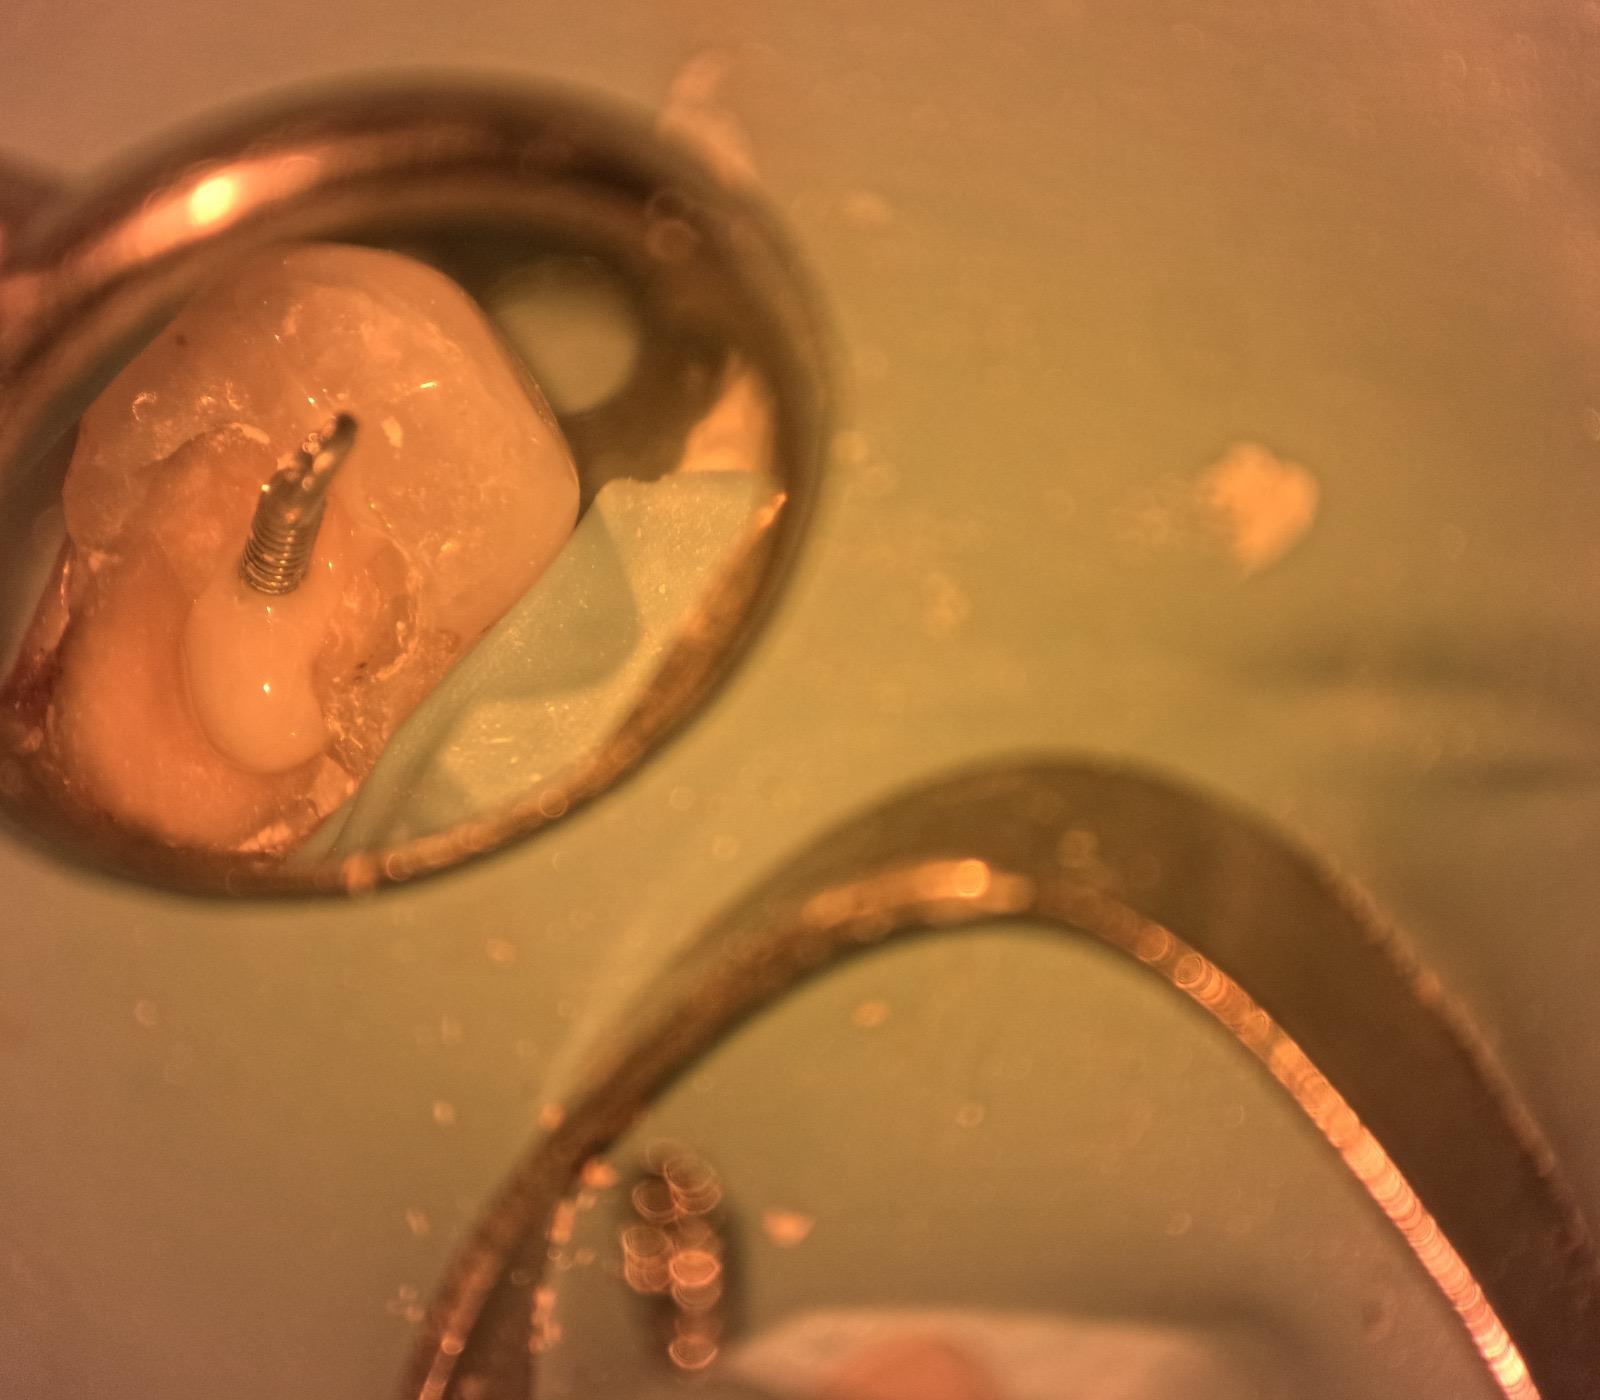

Obturation & Post Placement #4

● Placed a post and core as requested by the referring dentist

Post placement

Final PA#4 after post & core